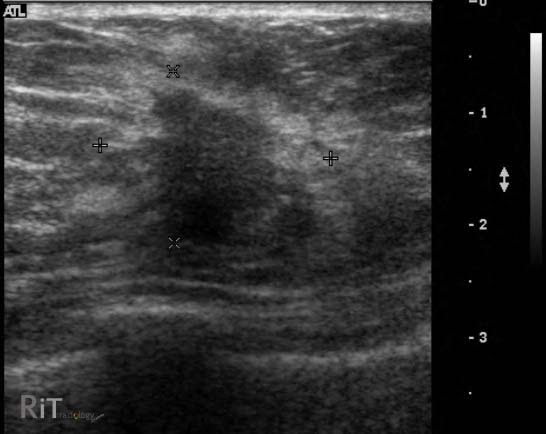

Una de las razones más comunes para realizar un ultrasonido mamario es la presencia de masas palpables o cambios en el tejido mamario que un médico o paciente ha detectado. Este tipo de ultrasonido permite a los médicos ver claramente la naturaleza de la masa, como su tamaño, forma y ubicación, así como distinguir entre un quiste lleno de líquido y una masa sólida que podría requerir una biopsia.

breast ultrasoundEl ultrasonido mamario también se indica para investigar síntomas específicos como dolor mamario, engrosamientos locales del tejido o secreciones del pezón. En estos casos, el ultrasonido puede proporcionar información valiosa sobre la causa de estos síntomas y ayudar a determinar el curso adecuado de tratamiento o seguimiento adicional necesario.

En algunos casos, un ultrasonido mamario se realiza como seguimiento de una mamografía donde se han identificado áreas de densidad o anomalías que no están claras. El ultrasonido es particularmente útil para proporcionar una visualización más clara de las áreas de interés y para ayudar en la toma de decisiones respecto a procedimientos diagnósticos adicionales.